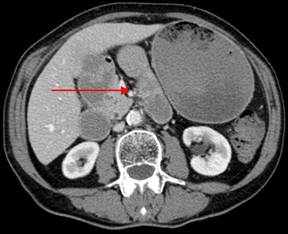

Initial laboratory tests were all within normal limits. She initially underwent a computed tomography (CT) scan of the abdomen that showed a duodenal obstruction at the ligament of Treitz (Figure 1). The patient then underwent an upper endoscopy that demonstrated a hemi-circumferential erythematous non-obstructing mass in the duodenum (Figure 2). Biopsies were taken that showed active enteritis and features of ischemia but no evidence of malignancy. Further blood testing was remarkable for a normal urine 5-hydroxyindoleacetic acid (5-HIAA) level and a slightly elevated chromogranin-A level 53 ng/mL (reference range: 0-50 ng/mL).

Figure 1. CT scan of the abdomen and pelvis. Note the dilated stomach with retained food particles. Arrow points to the duodenal mass. |